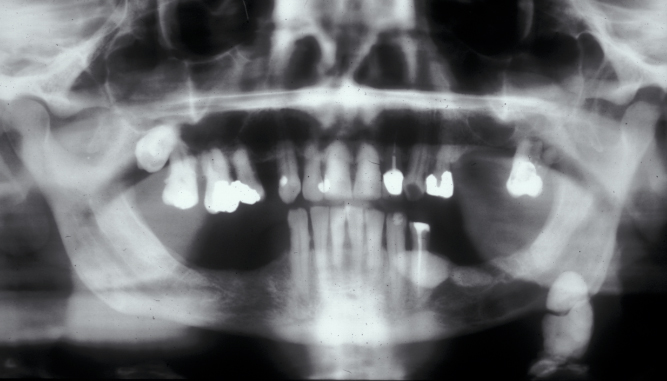

Approximately 80 % of salivary calculi occur in the ductal system of the submandibular glands. This is due to the greater length of the duct, its upward course and the thicker mucus secreted by the submandibular glands. There will usually be a history of painful, recurrent swelling in the submandibular region, particularly associated with eating or the anticipation of eating (pre-prandial swelling). Plain (X-ray) radiography will usually demonstrate a calculus in the duct (see Figure 1), or in the junction of the duct and gland or the gland itself (see Figure 2).

Figure 1: Calculus superimposed on a plain X-ray occlusal view of the anterior (front) floor of the mouth.

Figure 2: Calculi in the duct and the submandibular gland.

In the duct, a calculus is date shaped, at the junction of duct and gland it is comma shaped and in the gland it is round. Should a calculus not be visible on plain X-ray images, a sialogram is required which may demonstrate a radiolucent stone, a mucus plug or a stricture in the duct (see Figure 3).